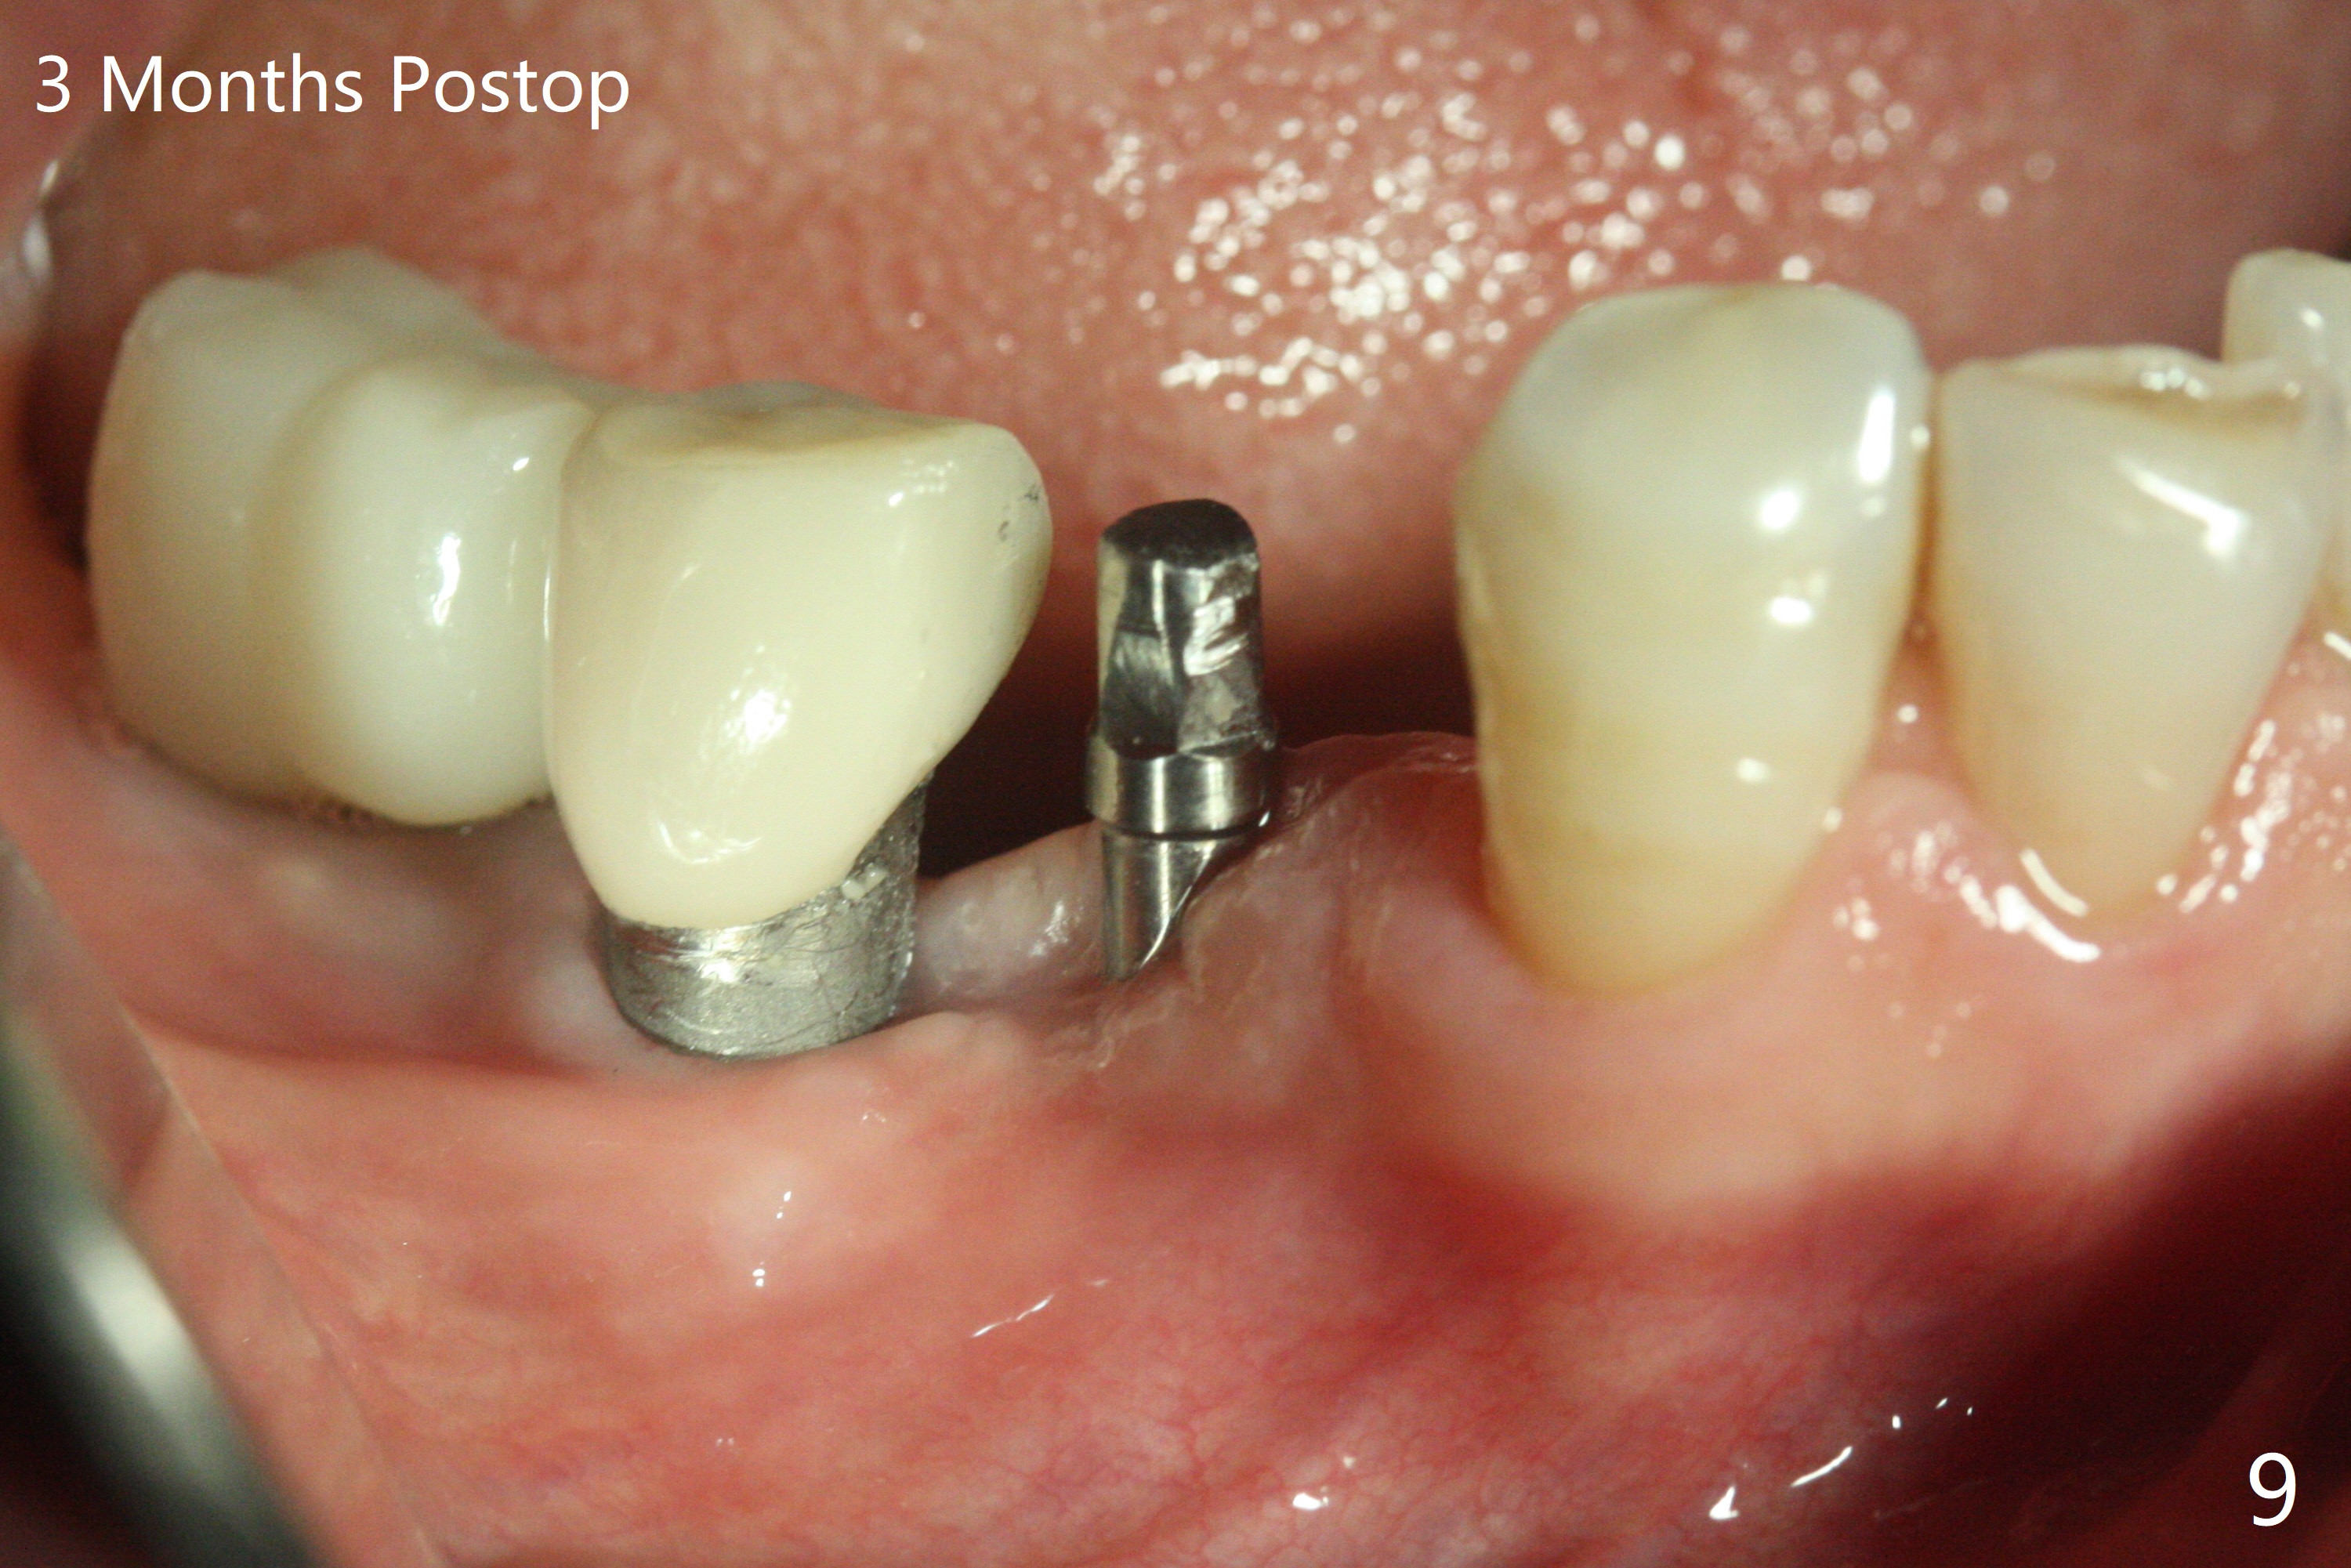

61岁女右下4(粘固后5.5年)植体周围炎(颊侧牙龈没有角化龈(图一:*)),因为颊侧种植(图二),翻瓣证实(图三),取出4.5毫米两段式植体,在舌侧骨质(图四:L)即刻植入2.5毫米一段式植体(图五),颊侧缺损植入大量粘性骨粉(图六:*),覆盖PRF膜后,缝合(图七),与图二对比,窄植体明显舌侧移位。术后一个月撤除牙周敷料(图八),并没有马上制作临时牙冠,让病人容易搞好局部卫生,促进伤口愈合(图九),术后三个月塞入龈线(图十:^),制备基台,植体在牙槽嵴中性位置(颊舌侧),但愿颊侧有足够再生骨质,覆盖植体螺纹。